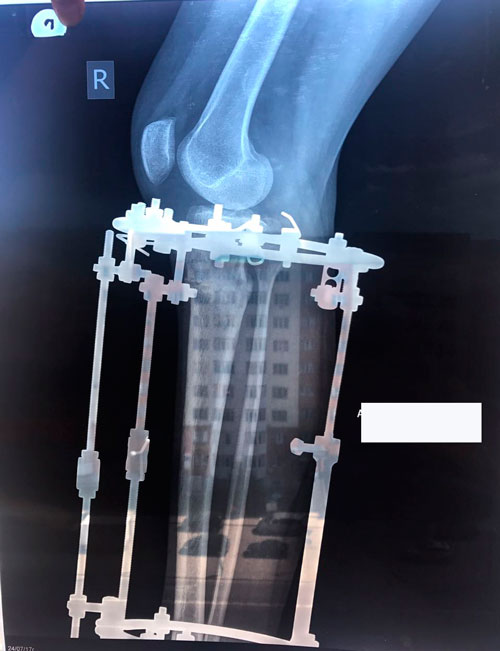

Исходник - 19 лет.

Дата операции 25.05.2017г.

В процессе круток

58 дней.

Через 2 недели можно на снятие аппаратов.

Срок лечения 75 дней.